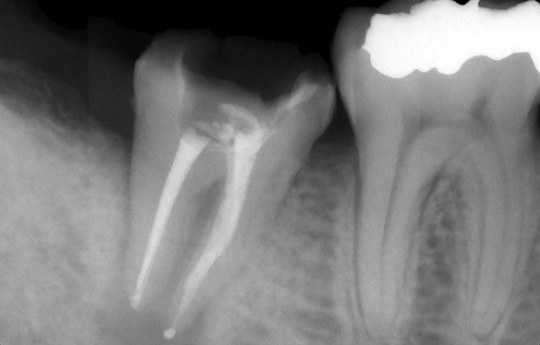

根の先の骨まで感染 骨が溶けている状態

数回の根管治療・根管充填の直後

根管治療終了から3か月 骨が回復傾向

かぶせものをして1年6か月

完全に骨は回復

また、根管(歯根の中にある管)からその周囲の骨に、虫歯由来の細菌が感染すると免疫反応により炎症を起こし骨が溶けます。これを根尖病巣と呼びます。根尖病巣は一種の歯周病であり、痛みが出にくいため放置されることが非常に多いです。そのままにしておくと、根の先の骨が大きく溶けつづけ、抜歯に至ることになります。

それを防ぐためには、感染源である根管の細菌を取り除き感染を止めることで、骨が再生する環境を作ってあげる必要があります。それが根管治療の目的となります。

その環境ができたら速やかに、しっかりと消毒をしたうえで根管を密に充填いたします。最終の土台やかぶせものの隙間から細菌が侵入しても密な根管充填が細菌の再侵入を遅らせてくれます。